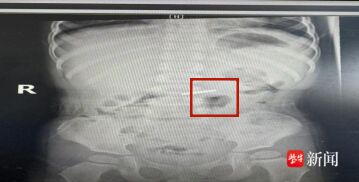

进入胃内后果然发现硬币,沿胃小湾侧达胃窦,通过幽门进十二指肠球部,均无异常及溃疡;倒镜拉近至胃底,使用予异物钳试着夹住硬币,但因异物钳无法旋转,夹住困难,拨动硬币至胃体中段,调整为正镜,尝试用异物钳夹住硬币后,慢慢退出,至贲门处后夹紧异物随贲门蠕动退进至食管内(警惕贲门撕裂),最后通过食管开口硬币顺利取出。

整个手术过程非常顺利,仅用了10分钟左右就顺利取出异物。取出的是一枚5角硬币,已经发黑,估计已经在胃里不少天。宝宝胃部还未发育完全,部分黏膜已经被异物剐蹭出血。